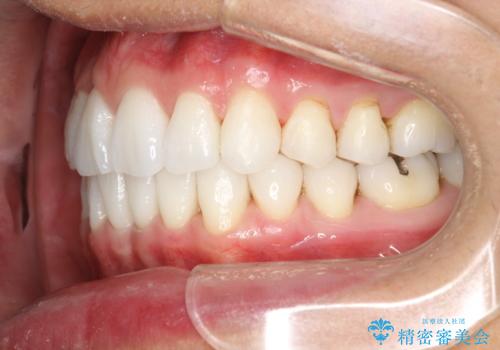

インビザライン終了時のPMTC

PMTC60分1万円+tax(保険適応外)を行いました。

インビザライン矯正治療は、歯にアタッチメント(歯を動かすための突起物)をつけます。そのため、矯正治療が終了し、アタッチメントを外すと着色が目立つことがあります。矯正治療の終了のタイミングではクリーニングを行い、着色の除去や歯と歯の間・歯と歯肉との境目などのケアをしっかりすることをおすすめしています。